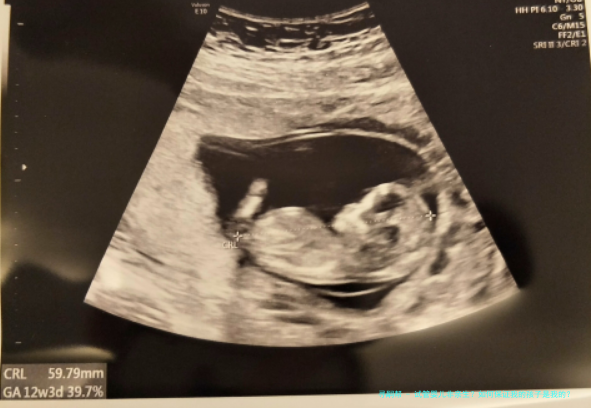

安徽“试管婴儿出生8年后被发觉放错胚胎”事件,引发注意。试管婴儿非亲生?怎么样保证我的孩子是我的?跟着人类人类辅助生殖技术的出世,给有生育困境的患者带来希望。辅助生殖技术不只是医药学技术,更是关涉到伦理问题,该怎样保障在辅助生殖技术过程顺当进行,需要从各个环节抓起,一环紧扣一环,每一步骤都至关重要。